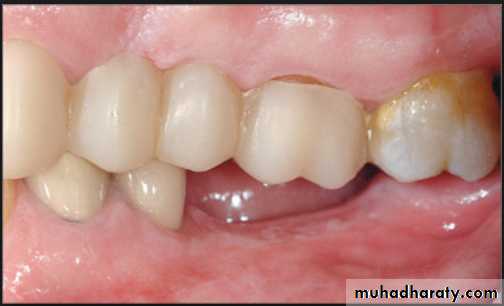

Interarch space

Lack of sufficient inter-arch distance- difficult for placing the teethFrequently it is caused by maxillary tuberosity that is too large in vertical height- surgical reduction vertical height is necessary for satisfactory replacement of the missing teeth.

• Treatment over erupted teeth

• If the tooth is extruded above the occlusal plane because of lack of an antagonist –• Treatment

• Moderately extrude tooth – aprox 2mm - enameloplasty.

• If the extrusion is greater than 2 mm or if the tooth does not lend itself to enameloplasty, the placement of a crown is indicated.

• If size of pulp prevent the required tooth reduction endodontic therapy

• If clinical crown length is inadequate crown lengthning

• Orthodontic treatment

• Severely extruded teeth – contacting the opposing ridge & if alveolar bone followed eruption remove the tooth and recontour the bone is necessary